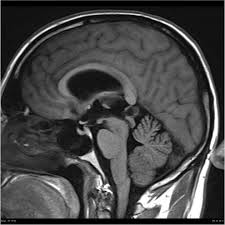

The diagnosis of pineal cyst is usually established by MRI with defined radiological criteria to distinguish benign pineal cyst from tumors of this area. A pineal cyst is usually only treated if it causes symptoms. In order to detect the presence of a cystic mass in the head magnetic resonance imaging is required.

Surgical removal is the most common treatment for pineal cyst. Pineal cysts tend to be more common in. The diagnosis of pineal cyst is usually established by MRI with defined radiological criteria to distinguish benign pineal cyst from tumors of this area. Surgical interventions have been used to remove the cyst and resolve symptoms37 These approaches include both. Some tumors are sensitive on radiationOutcome of the surgery depends on size and type of tumor. A neuro-ophthalmologist can be very helpful in defining vision and eye movement problems and can determine if these problems are related to the cyst. If symptoms are present your healthcare provider may recommend these treatments. Since your headaches might not be due to the pineal gland cyst discuss with your doctor other possible causes for your headaches. Pineal Cysts are fluid structures that form on the pineal gland and are treated when they are large greater than 2cm and cause symptoms such as debilitating headaches or eye movement problems.